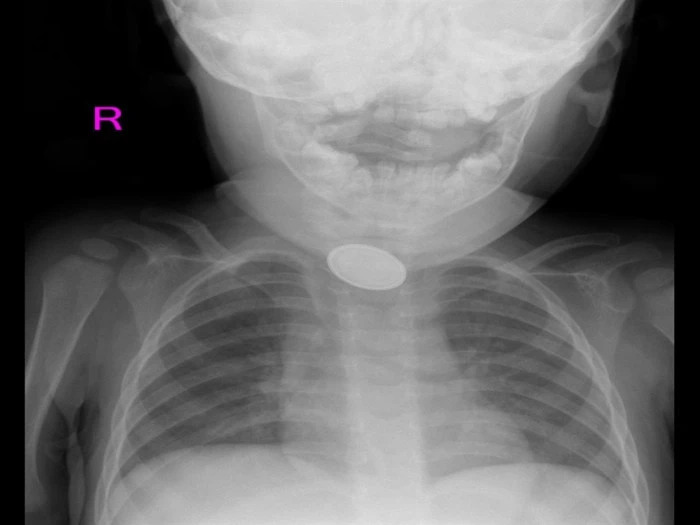

KAYSERİ'de 15 aylık A.Y.Ç.'nin yemek borusuna kaçan düğme pil ile lego oyuncak parçası, Kayseri Şehir Hastanesi'de yapılan 3 saatlik operasyonla çıkarıldı.

Kayseri'de 15 aylık A.Y.Ç.'nin yemek borusuna, evde oyun oynadığı sırada düğme pil ve lego oyuncak parçası kaçtı. O sırada yanında olan 4 yaşındaki kardeşi, 'Kardeşim lego yuttu' diyerek annesini çağırdı. A.Y.Ç.’nin ağızına bakan anne Tuğba Yılmaz, parçayı göremeyince dışkısından çıkacağını düşündü. Bir süre sonra A.Y.Ç.'nin yutma güçlüğü çektiğini gören Tuğba Yılmaz, Kayseri Şehir Hastanesi'ne başvurdu. A.Y.Ç.'ye yapılan röntgende, yemek borusunda düğme pil ve lego parçası oyuncağa rastlandı. Kız bebek A.Y.Ç., Kayseri Şehir Hastanesi Çocuk Cerrahisi ve Ürolojisi Anabilim Dalı Başkanı Doç. Dr. Mustafa Erman Dörterler ve ekibi tarafından ameliyata alındı. Yaklaşık 3 saatlik süren operasyonun ardından A.Y.Ç.'nin yemek borusuna kaçan düğme pil ile lego oyuncak parçası çıkarıldı.

Kayseri Şehir Hastanesi Çocuk Cerrahisi ve Ürolojisi Anabilim Dalı Başkanı Doç. Dr. Mustafa Erman Dörterler, "Hastamız 15 aylık bir bebek. Hastamız, disk pil ve beraberinde bir lego parçası yutmuş. Ben gece 01.30 gibi hastaneye geldim. Pili ve lego parçasını yutmasının üzerinden yaklaşık 6-7 saat geçmişti. Bu durumlarda dakika ve zaman çok önemli. 2 saatten sonra çok ciddi sıkıntılar oluşturabilecek hatta ölümle sonuçlanabilecek durumlarla karşı karşıya kalmaktayız. Ben, göğüs cerrahisi, çocuk gastroenteroloji, anestezi ekibi ve yardımcı sağlık personelleriyle beraber yaklaşık 20-25 kişiydik. Çocuğa, hızlı ve dikkatli bir şekilde müdahale ettik. Çünkü zaman ilerlediği için disk pil, yemek borusuna yapışmış ve delmek üzereydi. Dikkatli şekilde özenerek çıkarmaya çalıştık. Ekip çalışmasıyla beraber çıkarmayı başarabildik. Çocuğumuzun yoğun bakımdaki 2 günlük takip süreci devam ettikten sonra servisimize aldık. Şu an gayet iyi" diye konuştu.